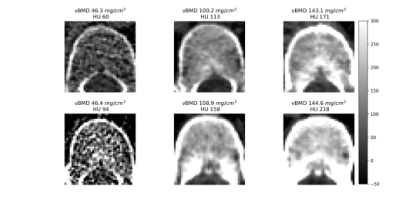

Figure 1. Intuitive comparison of features in vBMD measurement. The first row shows vertebral bodies with varying bone densities at 120 kVp. The second row shows corresponding vertebral bodies at non-120 kVp, where vBMD texture remains similar, but HU values within the VOI differ significantly. Low vBMD vertebral bodies exhibit both reduced HU values and a sparser trabecular structure in the measurement area